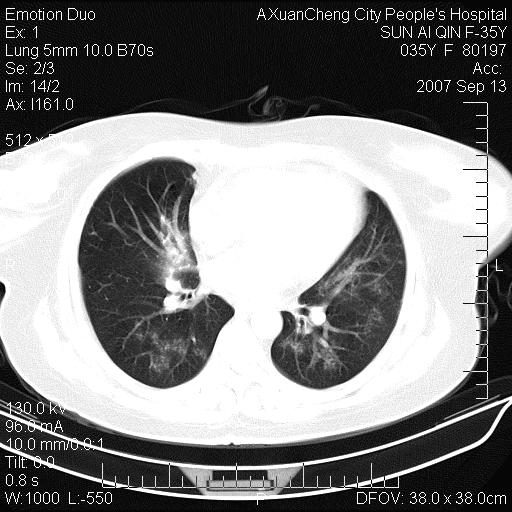

以下是引用天南地北在2007-9-13 13:43:00的发言:[br]考虑双肺、肺门侵润

以下是引用ydx_74在2007-9-13 15:42:00的发言:[br]仅看片,考虑右上肺癌并双肺转移,结合病史,考虑肺门、肺内淋巴侵润

以下是引用同在2007-9-13 15:08:00的发言:[br]支持肺门及双肺侵润.